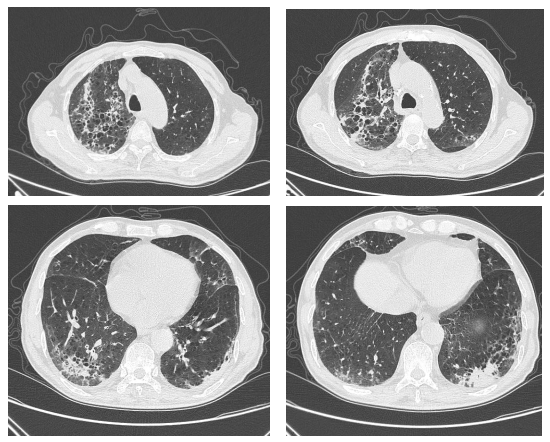

鹦鹉热衣原体肺炎影像学表现

图片尺寸780x584

图片尺寸785x466